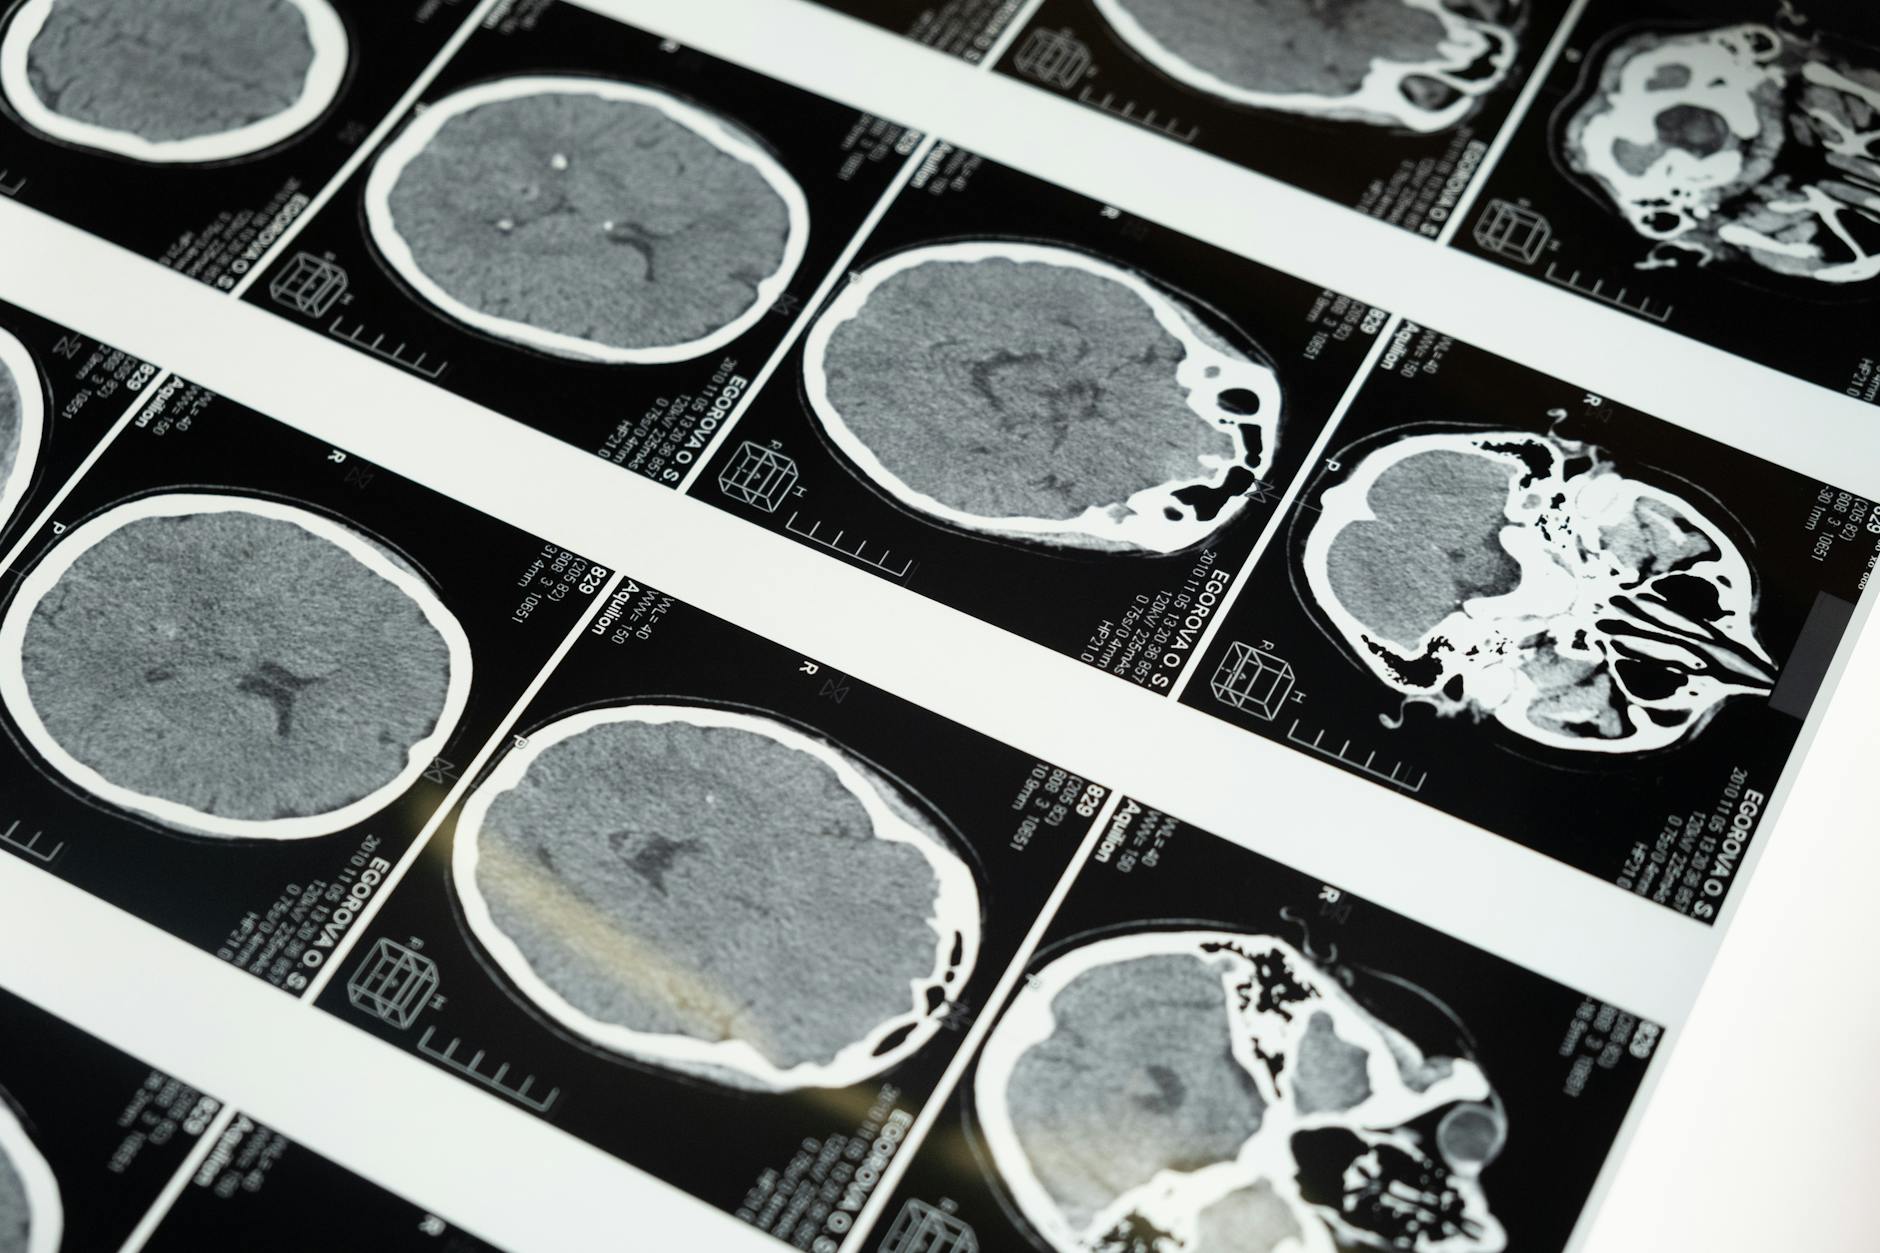

Bien que l’IRM soit souvent préférée pour évaluer les patients atteints d’algie vasculaire de la face, le scanner reste une alternative valide dans certaines circonstances. Le choix entre ces deux techniques dépend de plusieurs facteurs :

- L’IRM offre une meilleure résolution des tissus mous du cerveau, particulièrement utile pour détecter les lésions tumorales ou inflammatoires subtiles

- Le scanner est plus rapide et peut être réalisé en urgence si une pathologie aiguë est suspectée

- L’IRM est contre-indiquée chez les patients porteurs de certains implants métalliques

- Le scanner utilise des radiations ionisantes, tandis que l’IRM n’en utilise pas

Pour l’évaluation spécifique d’une algie vasculaire de la face, l’algie vasculaire de la face scanner peut être prescrit comme alternative si l’IRM ne peut pas être réalisée. Cependant, l’IRM reste l’examen de choix du fait de sa supériorité diagnostique pour visualiser les structures cérébrales fines.

Protocole d’imagerie recommandé

Lorsqu’une IRM est décidée, le protocole comprend généralement :

- IRM cérébrale haute résolution avec coupes multiples

- Séquences pondérées en T1 et T2

- Injection de produit de contraste (gadolinium) pour évaluer l’intégrité de la barrière hémato-encéphalique

- Angio-IRM pour visualiser les vaisseaux intracrâniens si une pathologie vasculaire est suspectée

Cette approche systématique maximise les chances de détecter une cause secondaire si elle existe. Cependant, même avec ce protocole complet, la plupart des patients atteints d’AVF auront des résultats d’imagerie normaux.